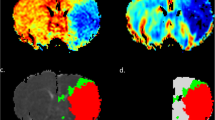

In Fig. 2, we present the maps of DTI metrics acquired at 0.5 h after middle cerebral artery occlusion. The maps of L, axial diffusivity, radial diffusivity, MD, and p exhibited initial hypointensity changes in the ischemic areas, whereas the maps of the remaining metrics displayed symmetrical signal intensity. Figure 2 presents the labels for the penumbra, IC, NT, and contralateral hemisphere. The NCA indicated that 25 features would yield the minimum generalization error (Supplementary Table S1). Thus, all 25 features were used for subsequent modeling.

Eleven DTI-derived maps and the corresponding labels for a rat at 0.5 h after MCAO. Each of the 11 DTI-derived maps is displayed along with the corresponding label for a rat at 0.5 h after MCAO. All maps have been normalized to the same grayscale for visual consistency. In the label, red indicates the IC, green indicates the penumbra, blue indicates the NT region, and yellow indicates the contralateral hemisphere. AD Axial diffusivity, Cl Linear tensor, Cp Planar tensor, Cs Spherical tensor, DTI Diffusion tensor imaging, FA Fractional anisotropy, IC Ischemic core, L Total magnitude of diffusion tensor, MCAO Middle cerebral artery occlusion, MD Mean diffusivity, NT Normal tissue, RA Relative anisotropy, RD Radial diffusivity, p Pure isotropic diffusion, q Pure anisotropic diffusion

Table 4 presents the performance of the stacking model in penumbral segmentation for the test rats. The median ML-estimated PV was 106.4 (IQR 44.6–157.3) mL, whereas the median PDM-defined PV was 102.0 (52.1–144.9) mL. The overall metrics for evaluating penumbra segmentation revealed a median DSC of 0.61 (0.40–0.80) and a volume similarity of 0.88 (0.79–0.96). Figure 3 presents the results of a comparison of ML-estimated penumbra segmentation with the corresponding PDM-defined penumbra segmentation for two test rats. In the suture-occlusion model, at 1.5 h, the penumbra was relatively small (even sparse) in areas at the margin of a large IC. Notably, reduced DSC (0.52) and volume similarity (0.73) were observed in the rat with a relatively small extent of the penumbra, suggesting that DSC is highly sensitive to geometric changes and only considers the overlap.

Application of the trained stacking model to two rats. In this study, PWI and DTI were acquired once and twice, respectively. Subsequently, PDM maps at 0.5 and 1.5 h after stroke onset were generated by registering mean MD maps at 0.5 and 1.5 h to PWI, respectively. IC regions are represented in red, penumbra regions in green, and NT regions in blue. The stacking model was trained using data from 15 rats and then applied to the remaining rat. DSC Dice similarity score, DTI Diffusion tensor imaging, IC Ischemic core, MD Mean diffusivity, ML Machine learning, NT Normal tissue, PDM Perfusion–diffusion mismatch, PWI Perfusion–weighted imaging